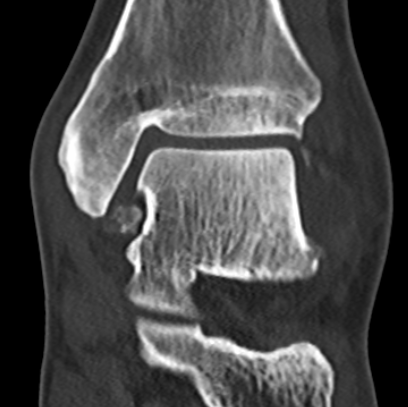

Talus ostechondral lesions

Posterior talus osteochondral lesions